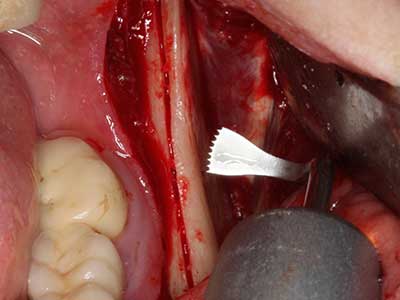

Piezo surgery has additional advantages when harvesting bone blocks. In addition to the high precision with osteotomy described above, the use of the thin saw tips specifically minimizes loss of material. Greater loss of material during harvesting can be expected with the thicker instrument tips, particularly when using Lindemann drills (Lakshmiganthan, Gokulanathan et al. 2012). The basal separation, which is necessary particularly for retromolar block transplants, is simplified by specially designed rectangular saws, with the result that piezo surgery is viewed as a precise, simple and safe procedure for harvesting retromolar bone blocks (Happe 2007) (Fig. 1-12).